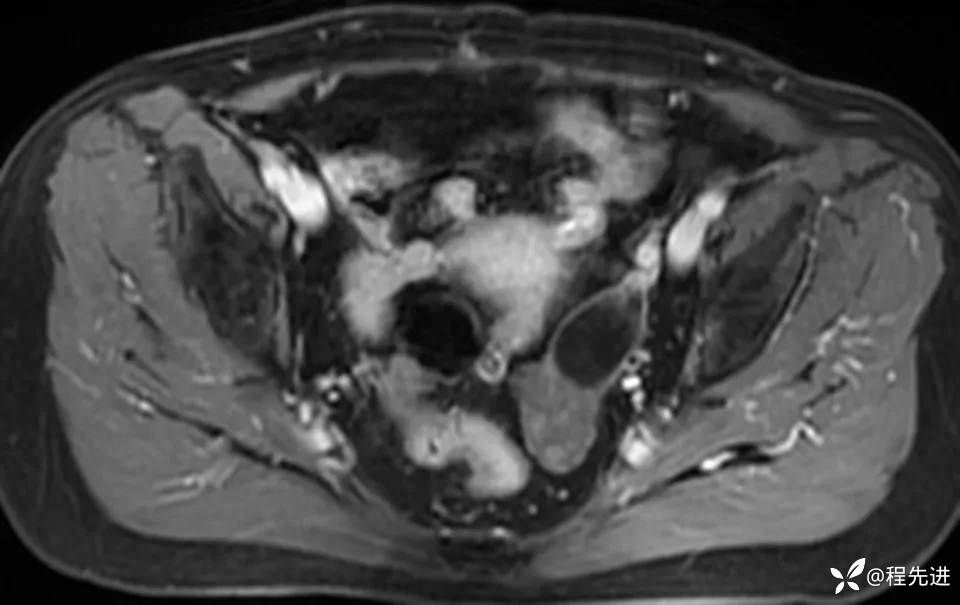

MRI平扫+增强:

img